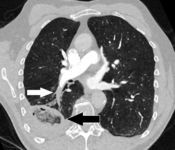

Segmental and subsegmental pulmonary emboli on both sides

CT pulmonary angiography showing a "saddle embolus" at the bifurcation of the main pulmonary artery and thrombus burden in the lobar arteries on both sides.

Pulmonary embolism (white arrow) that has been long-standing and has caused a lung infarction (black arrow) seen as a reverse halo sign.